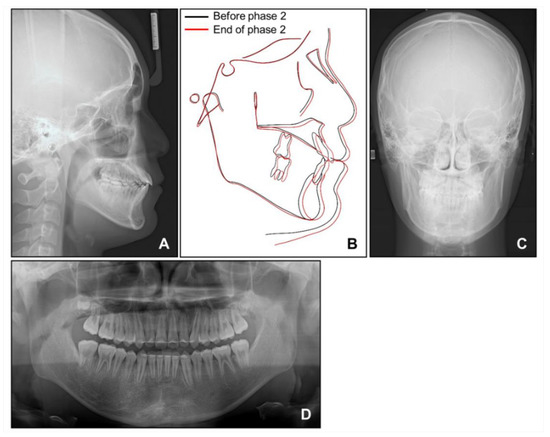

When the patient reached 13 years of age, he claimed that his teeth were still not fitting well. He showed a mild chin point deviation toward the right side, and severe lip canting while smiling was still present. The lateral facial profile was maintained favorably after the phase 1 treatment, but the Becker’s nevus area on the right cheek through the upper neck was more prominent, with hypertrichosis (Figure 7 and Figure 8). Intraorally, all permanent teeth except the second molars had successfully erupted; however, the hypertrophic region in the anterior mandible was still present. Therefore, he showed severe canting of mandibular anterior teeth with a 1 mm deviation of the apical base midline of the mandibular dentition toward the right side.

At this point, we noticed that the nevus, facial asymmetry, lip canting, and hypertrophy of alveolar bone occurred in the same area. Taking into consideration these symptoms, we suggested the presence of “Becker’s nevus syndrome” for the simultaneous occurrence of Becker’s nevus and other systemic anomalies. We interviewed the patient, and he informed us that he had been recently diagnosed with scoliosis by an orthopedist (Figure 8D). Fortunately, the severity of the scoliosis was incipient to moderate, with no need for active treatment but only a need for observation.

Figure 8. Radiographs before phase 2 treatment: (A) Lateral cephalogram; (B) Posteroanterior cephalogram; (C) Panoramic radiograph; (D) Standing anteroposterior radiograph of spine showing scoliosis.